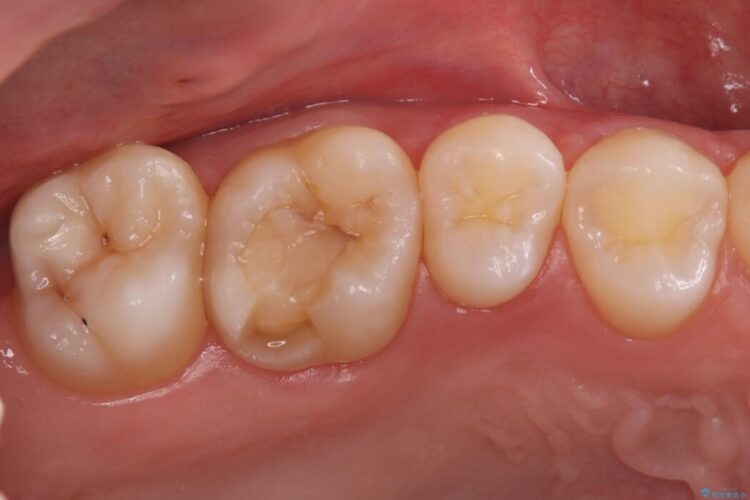

右上奥歯が欠けてしまい来院されました。

右上6番の舌側が欠けてしまっている状態でした。

破折リスクを考慮し、セラミックアンレーで治療を行うこととしました。